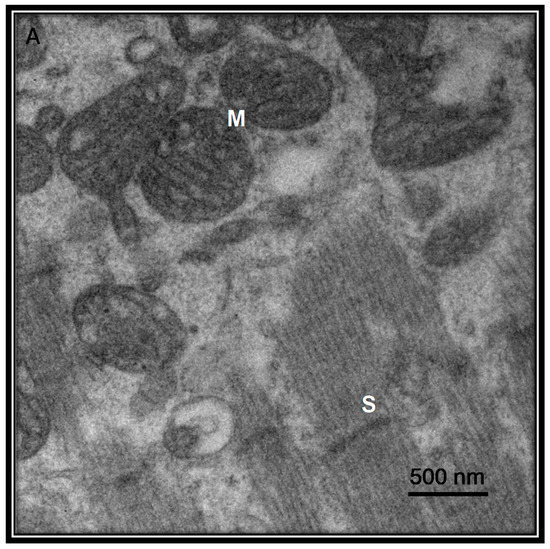

高血圧や心筋損傷は、レニン・アンジオテンシン・アルドステロン系(RAAS)の阻害薬で治療されることが多く、ACE2受容体のレベルを上昇させる可能性がある。最近の報告では、心筋損傷がSARS-CoV-2と関連していることが示唆されている。図4は、COVID-19死後にウイルスの存在を示す患者からの心臓サンプルの超質的特徴を示す。しかし、比較のために図5は、ウイルス粒子のないコントロール被験者としての心臓サンプルの超構造を示している。

図4 COVID-19死後の患者からの心臓サンプルの超構造

この患者は当院の68歳女性で、II型糖尿病、虚血性心疾患、高血圧、病的肥満を併存していた。電子顕微鏡の40,000×の写真はJeol JEM-1011電子顕微鏡で撮影したものである。写真は、細胞質の喪失と内膜の喪失、外膜の変質を伴うチョークの喪失と短縮、心臓線維の破裂を伴う心臓内のウイルス粒子を持つ間繊維状ミトコンドリアを描写している。略語。M=ミトコンドリア、S=サルコメア、VP=ウイルス粒子。

図5. ウイルス性粒子を含まない対照被験者としての心房細動を有する54歳女性患者の生検死後の心臓サンプルの超構造的特徴

ミトコンドリアは規則的な隆起と短いサルコメアを示す。電子顕微鏡写真はJeol JEM-1011電子顕微鏡を用いて40,000倍に拡大した。略語。M=ミトコンドリア、S=サルコメア。